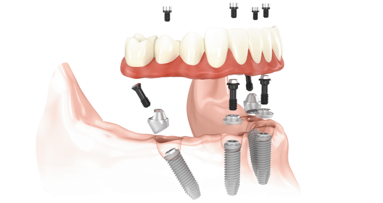

Pro Arch od společnosti Straumann je koncept, který zahrnuje různá léčebná řešení pro zcela bezzubého pacienta. Cílem je poskytnout ...

Ztráta chrupu je ranou známkou stárnutí s nepopiratelným dopadem na každodenní život a sociální interakci lidí na celém světě.